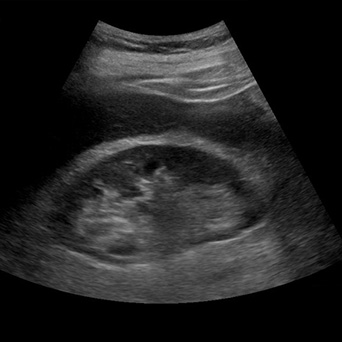

Abdominal Ultrasound

- Appropriate probe selection, gain, depth, and positioning

- FAST scan space identification

- Right and left upper quadrant views

- Suprapubic region (two planes)

- Recognition of free fluid vs organ-related fluid

- Identification of parenchymal organs (liver, kidneys, spleen)

- Gallbladder and urinary bladder